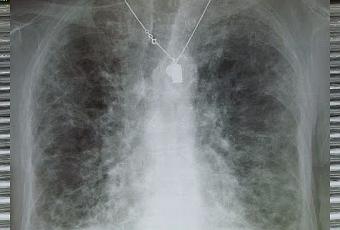

Fibrose pulmonaire.

Source iconographique: https://fr.wikipedia.org/wiki/Fibrose_pulmonaire#/